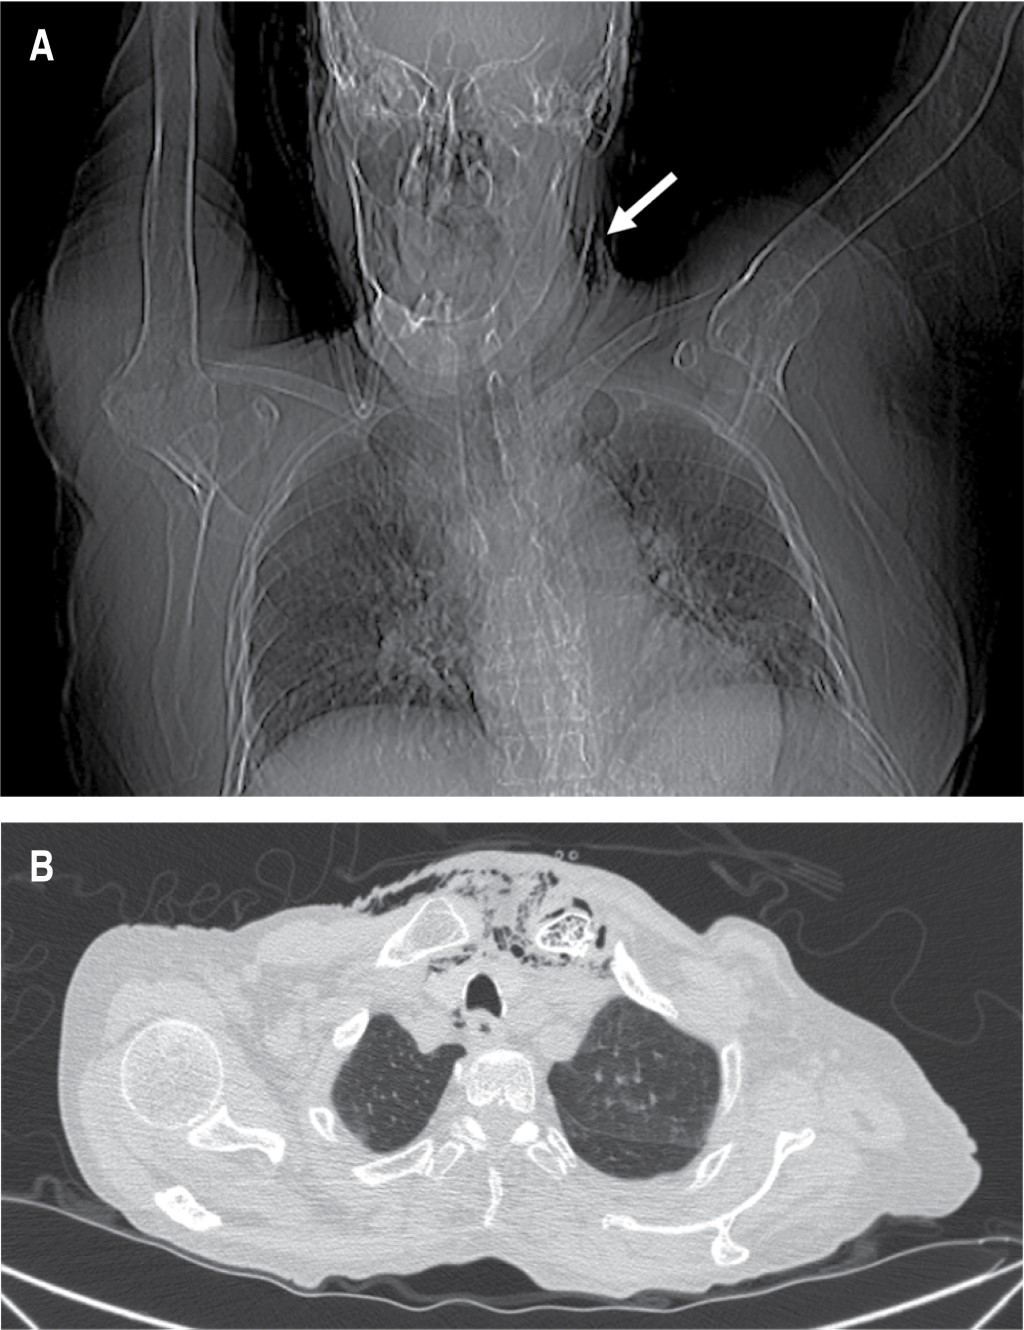

Durante el abordaje inicial en el servicio de urgencias, se decidió la colocación de sonda urinaria (la paciente aún tenía diuresis espontánea), con evidencia de piuria; se intentó colocar un acceso venoso central, palpando la presencia de enfisema subcutáneo, por lo que se solicitó realizar una tomografía computarizada; con reporte de un proceso inflamatorio localizado en la región cervical con extensión al mediastino superior, así como presencia de gas intramedular en clavícula izquierda y manubrio esternal, sugestivo de osteomielitis (Figuras 1 y 2). El estudio del líquido peritoneal obtenido a través del catéter de diálisis se encontró dentro de parámetros de referencia, por lo que ante la evidencia de choque séptico asociado a evidencia radiológica de mediastinitis Endo IIA, se propuso tratamiento quirúrgico urgente consistente en exploración y drenaje cervical, el cual no fue aceptado por los familiares de la paciente hasta 12 horas después del ingreso hospitalario. Se inició tratamiento antibiótico de amplio espectro (carbapenémico) desde el ingreso hospitalario y durante la cirugía se realizó un abordaje cervical en collar, 1 cm por encima de la escotadura esternal, se disecó por planos y se identificó presencia de líquido purulento proveniente de la articulación esternoclavicular izquierda; debido a la inestabilidad hemodinámica de la paciente, manifestada por hipotensión persistente, uso de aminas presoras con dosis progresivas y presencia de extrasístoles ventriculares, se decidió limitar la cirugía a control temporal del foco infeccioso con drenaje, irrigación y debridación parcial del área afectada.